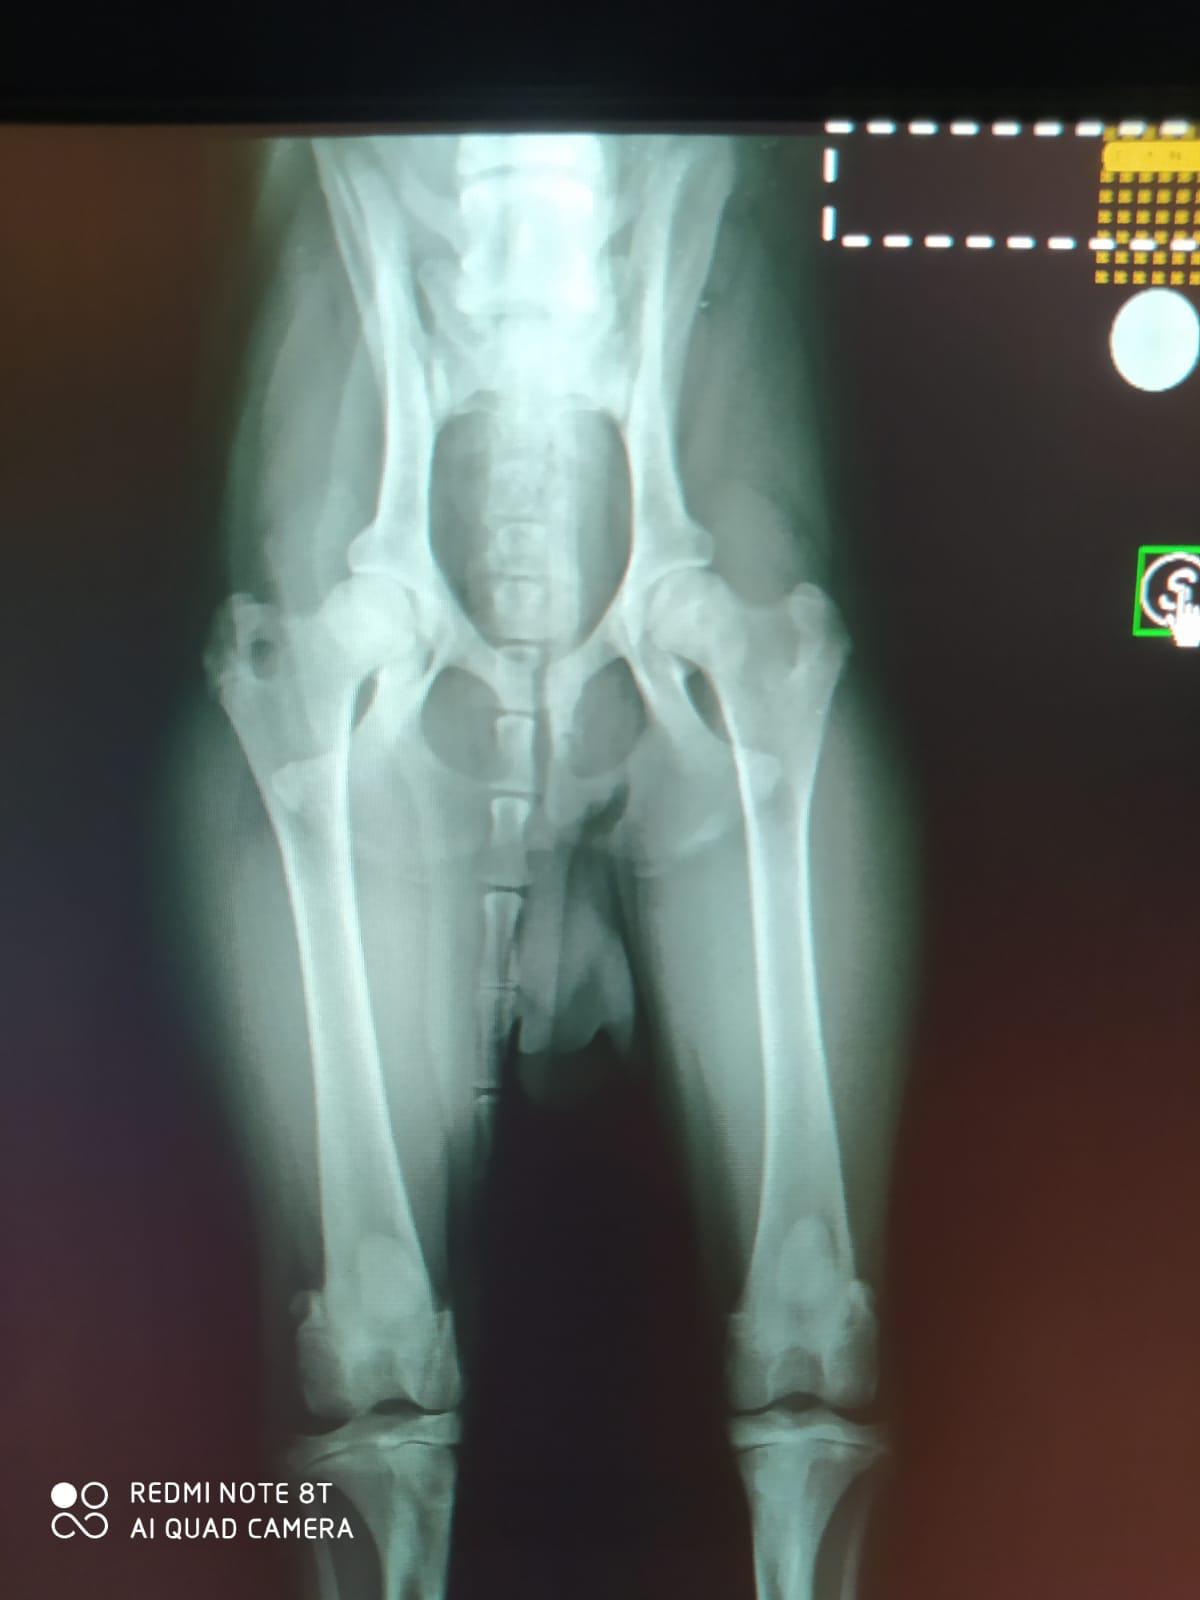

Er hat sich schon gut eingelebt. Bill ist ein sozialer Rudelhund; braucht aber die anderen Hunde nicht unbedingt.Er liebt die Menschen und hat viel "will to please".Seine Kontrolluntersuchung bezüglich seiner Operationen ist sehr zufriedenstellend verlaufen. Allerdings wies der Orthopäde darauf hin, dass Bill durch die Operationen ein erhöhtes Risiko für einen Kreuzbandriss hat und man im Laufe seines Lebens auch leider damit rechnen muss. Nun beginnt für ihn die Physiotherapie und ein langsamer Muskelaufbau.